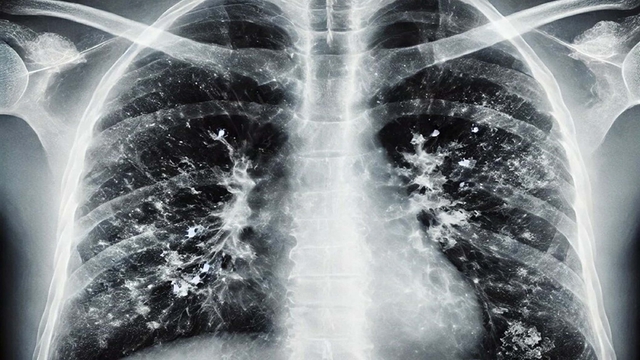

Özellikle 65 yaş üstü vatandaşlara yönelik uyarılarda bulunan Prof. Dr. Şener, "Bu grupta RSV dediğimiz viral enfeksiyon önem taşıyor. RSV, akciğerde yaygın enflamatuar tabloya sebep oluyor. Bunun da aşısı var. Cebinizden ücret ödeyerek yaptırabileceğiniz bir aşı. Özellikle 75 yaş üstü bireylerin mutlaka olması gerekiyor. 65 yaş üstünden başlarsak viral enfeksiyonlar ağır seyrediyor. Koronavirüs döneminde bunlara alışkındık; pandemi sonrasında da ağır viral enfeksiyon tablolarıyla karşı karşıya kalmaya başladık. Ciddi solunum yetmezliği, ateş, üşüme ve titreme semptomları; acil servise başvuru ve oksijen desteğine rağmen toparlanamama gibi durumlar görüyoruz. Bu nedenle bu hastalar, bazen normal servise bazen de yoğun bakıma yatmak zorunda kalıyor. Bu hastalar maalesef bazen her türlü tedaviye rağmen akciğerdeki ağır enfeksiyonun yaygınlaşmasıyla ölüme kadar ilerleyebilen klinik tablolara sebep olabiliyorlar" diye konuştu.

Hastalığı ayakta geçirenlere yönelik de değerlendirmelerde bulunan Prof. Dr. Şener, "Hafif geçirseler bile akciğerlerdeki hasar ilerleyen dönemlerde KOAH ve astım gibi tablolara sebep olabiliyor. Sonrasında ömür boyu ilaç kullanmak zorunda kalıyorlar. Bu konu da önemli. Bir diğer tablo ise kalp hastalığı, hipertansiyon ve diyabeti olanlar. Bu kişiler de ağır klinik tablolar geçiriyor. Atlattıktan sonra bakteriyel enfeksiyonlar sık görülüyor. Viral enfeksiyonu hastanede atlattıktan sonra geçmeyen öksürük nöbetleri ve balgam yaşanıyor. Bundan sonra da zatürre dediğimiz tablolar oluşuyor. Bu durumda kesinlikle antibiyotik alınması lazım. 65 yaş üstü gruba mesaj gitmesi gerekirse; hafif bir gribal enfeksiyon geçirdikten sonra öksürük ve balgam devam ediyorsa, uzman doktora veya aile hekimine mutlaka görünmek gerekiyor. Belki de zatürre oldunuz ve farkında değilsiniz. Gerekli tetkiklerin yapılması ve antibiyotik başlanması lazım" dedi.